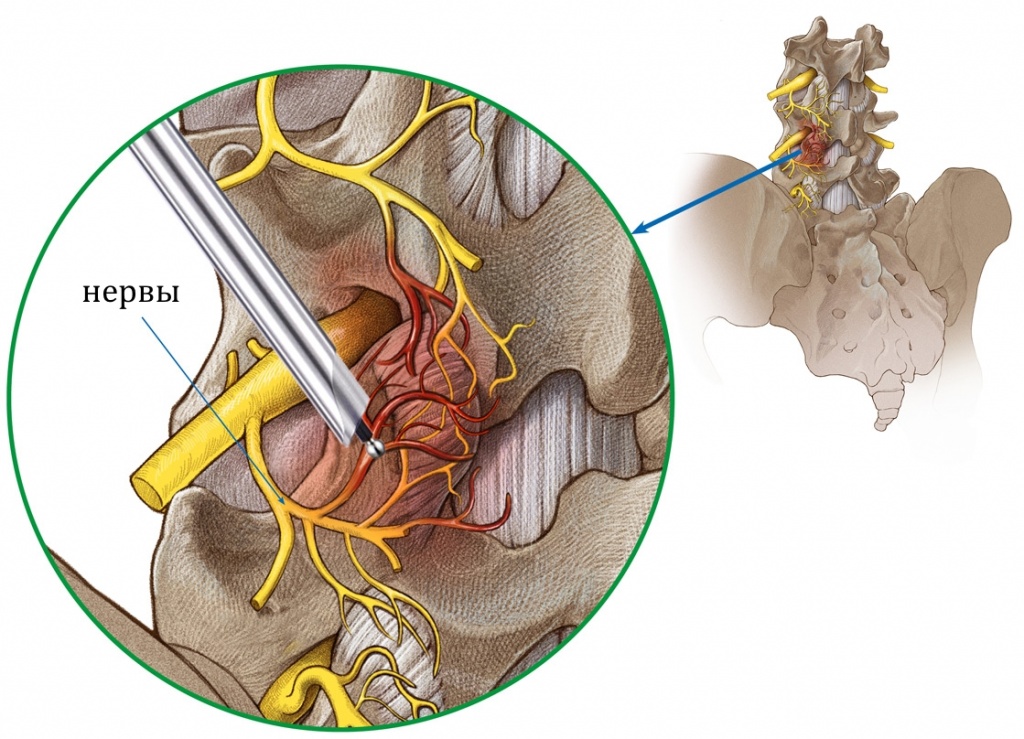

Остеоартрит фасеточных суставов: медицинские снимки и схемы